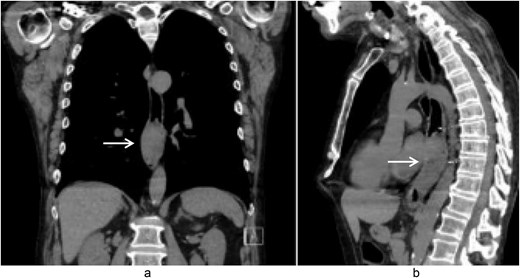

A 58-year-old male with a history of hypertension, daily alcohol use, and 35 pack year smoking history presented with progressive dysphagia and significant weight loss over a period of 3 months. His symptoms began with heartburn, with initial failure of empiric treatment for reflux. He then developed dysphagia to solids that progressed to liquids and eventually an inability to tolerate his own saliva. Over that timeframe, he also noted unintentional weight loss of ~30 lbs. He eventually presented to the emergency department where a CT scan raised concern for an obstructing esophageal mass (Fig. 1). He urgently underwent upper endoscopy revealing a large polypoid tumor with a broad base located in the lower esophagus (Fig. 2). Biopsies revealed a high-grade malignant neoplasm with spindle cell features concerning for a sarcoma. Further workup with brain MRI and positron emission tomography (PET) scan confirmed a hypermetabolic esophageal mass without evidence of distant metastatic disease (Fig. 3). Unfortunately, endoscopic ultrasound was unable to be performed given the nearly obstructive nature of the tumor.

Endoscopic images (a and b) of a nearly obstructive intraluminal esophageal mass.